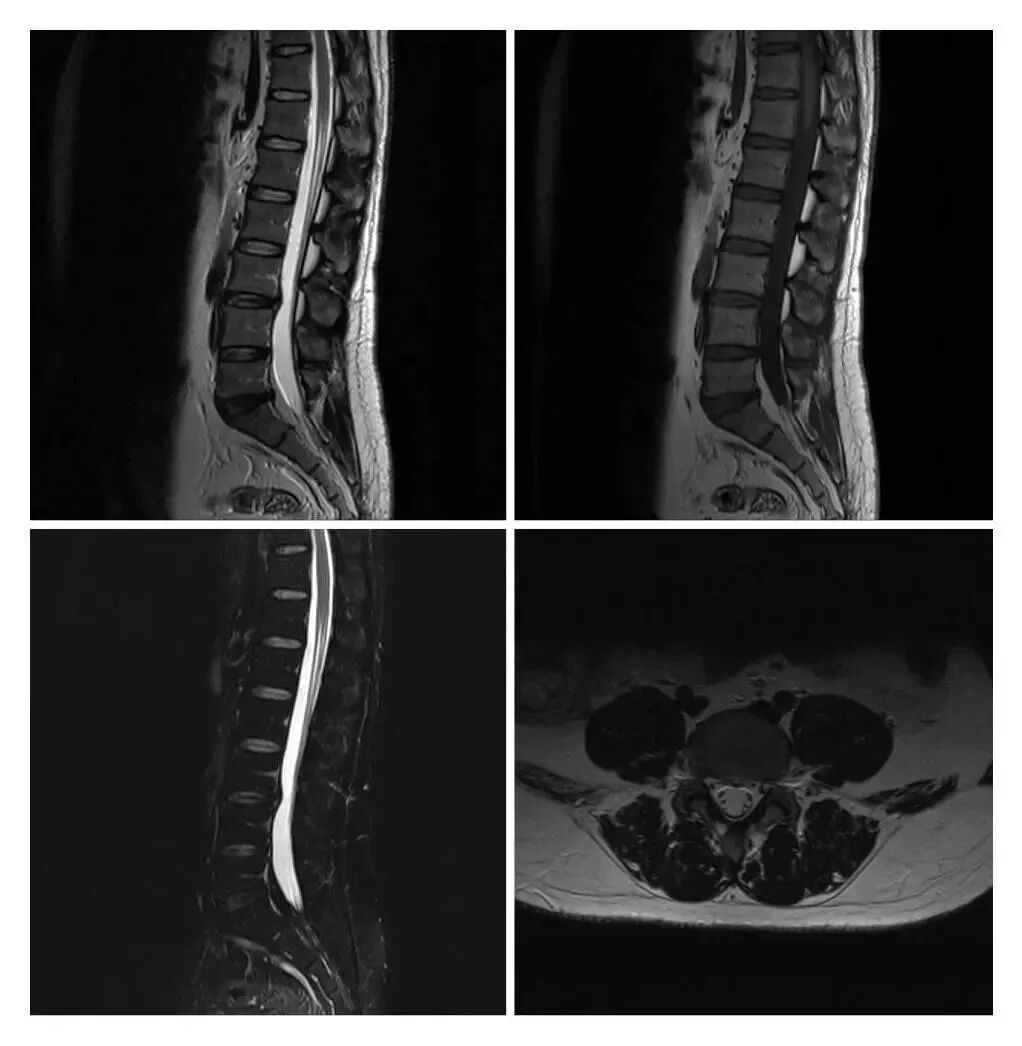

MRI現(xiàn)已應(yīng)用于全身各系統(tǒng)的成像診斷。效果最佳的是顱腦,及其脊髓、心臟大血管、關(guān)節(jié)骨骼、軟組織及盆腔等。而且不同于已有的成像術(shù),它對疾病的診斷具有很大的潛在優(yōu)越性。多序列成像、多種圖像類型,為明確病變性質(zhì)提供更豐富的影像信息,能很好的滿足臨床的診斷需求。

滑動查看更多